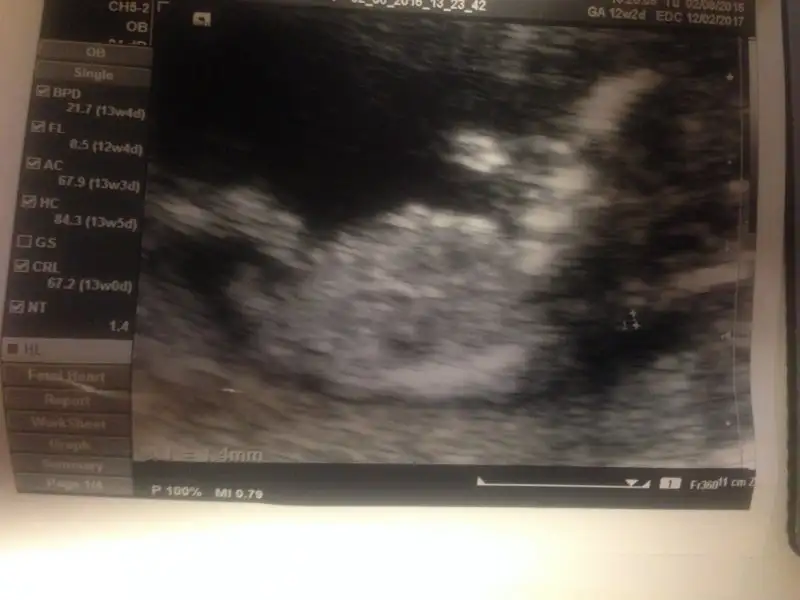

İlki cumartesi aldım ikincisi bugüne ait. Bugünkü çok karanlık.

cumartesi günkü yaptı erkek gibi dedi. ama bugünkü çok da uğraşmadı döndürmek için falan göstermiyor dedi. bu cumartesi tekrar kendi doktoruma gideceğim için de ısrar etmedim.Maşallah bebişe:) ben hiç anlamam ama 2. Resimde sanki baya erkek çocuğu görüyorum yaDr Bi yorum yaptı mı